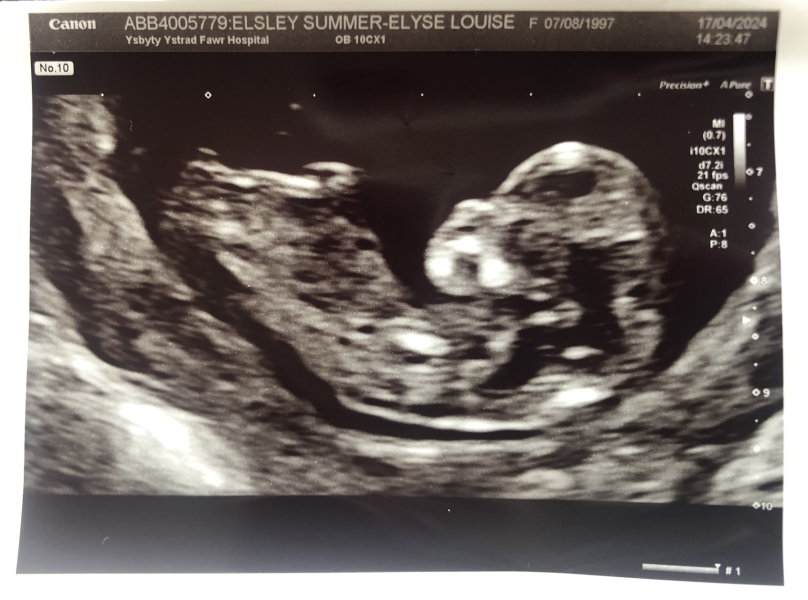

Anyone know how to use the nub theory? Did sneak peak at 6 weeks so should be a girl according to that. Does the scan look like a girl?

OCTOBER 2024 BABIES :) THREAD 3

WickWood · 17/04/2024 17:07

@SELE97 I'd have guessed boy, but I have absolutely no clue really! I think the sneak peak is highly accurate, so the baby must be a girl?!

SELE97 · 17/04/2024 17:27

@WickWood we had it done at a clinic too so it should be accurate. However because I'm not as far along as I thought I was, I'm worried we did the sneak peak too early, and there wasn't enough fetal DNA in my blood yet. Doesn't matter either way, I'm just interested in the nub theory☺️

WickWood · 17/04/2024 17:40

@SELE97 Apparently there's a really active group on FB where people can guess quite accurately!

@Missingpotatocroquettes @CluelessInLondon my "bump" looks like @SELE97's at 14+3. It's my first so I wasn't expecting one so early. Im a size 10 so it's quite noticeable. Clothes are getting tricky.

@SELE97 yes girl